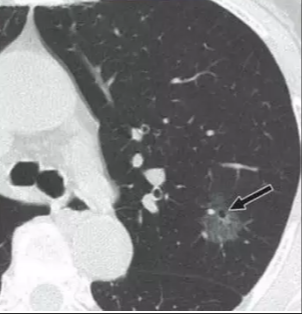

但如果有CT上有这些征象要高度警惕了!!!

1、毛刺征

2、血管征

3、胸膜牵拉征

4、空泡征

5、血管穿行征

6、空气支气管征

有以上征象,不论结节大小,要高度警惕肺癌可能!